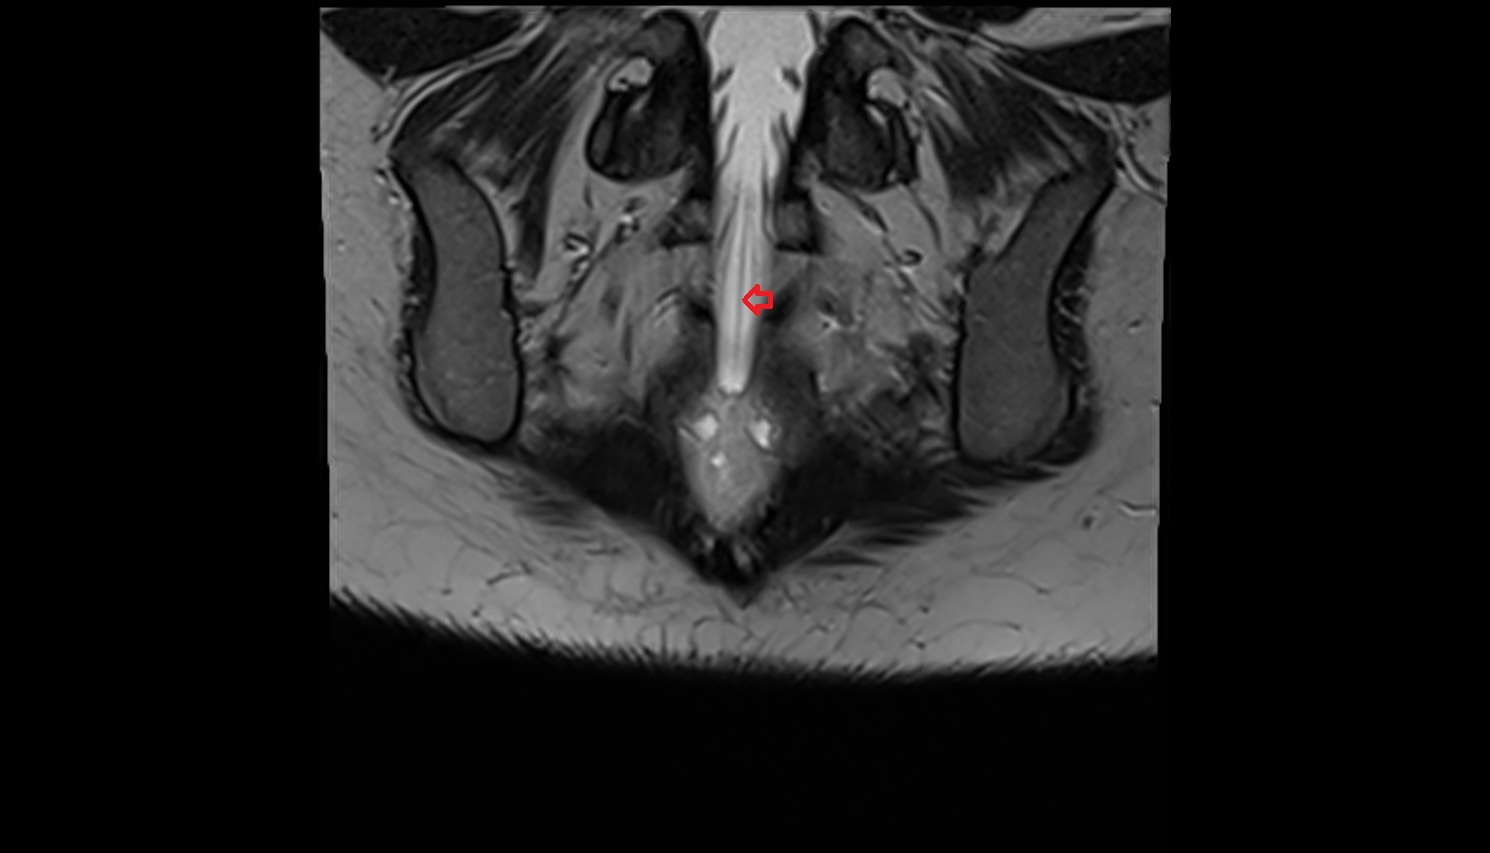

- Peripheral zone of prostate

- Anterior Fibromuscular Stroma of prostate

- Central zone of prostate

- Transitional zone of prostate

- Membranous urethra

- Prostatic urethra